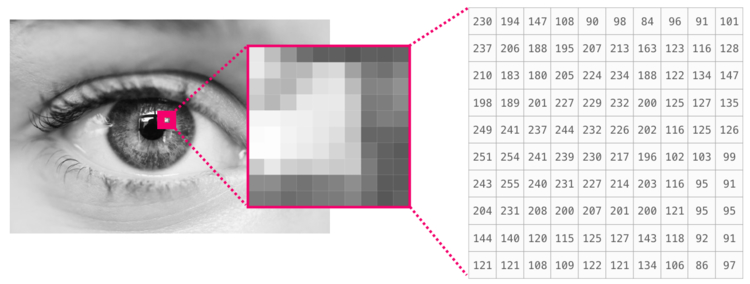

Классификатор фотоизображений АФ глазного дна по типам:

- норма

- минимальные изменения

- фокальное усиление

- пятнистый патологический паттерн

- линейный

- крапчатый

- сетчатый

- кружевоподобный.

- Гндоян И.А., Петраевский А.В., Дятчина А.И. Аутофлюоресценция глазного дна в диагностике возрастной макулярной дегенерации. Вестник офтальмологии. 2020;136(5):136‑141.

- Обработка изображений с помощью библиотеки Python Pillow

- Ильясова Наталья Юрьевна Диагностический комплекс анализа изображений сосудов глазного дна // Биотехносфера. 2014. №3 (33). URL: https://cyberleninka.ru/article/n/diagnosticheskiy-kompleks-analiza-izobrazheniy-sosudov-glaznogo-dna (дата обращения: 13.12.2022).

- РАЗРАБОТКА МЕТОДА И АЛГОРИТМА СЕГМЕНТАЦИИ КРОВЕНОСНЫХ СОСУДОВ НА ИЗОБРАЖЕНИИ ГЛАЗНОГО ДНА

- OpenCV Python Program to analyze an image using Histogram

- 1.2.2 Методы анализа цифровых изображений

- Обработка изображений в цифровой фотографии. Анализ гистограмм

- Гистограмма изображения и выравнивание гистограммы

- Чтение гистограммы на примере цветной фотографии

- Что такое гистограмма?

- Гистограммы камер: цвет и контраст

- Гистограмма (фотография)